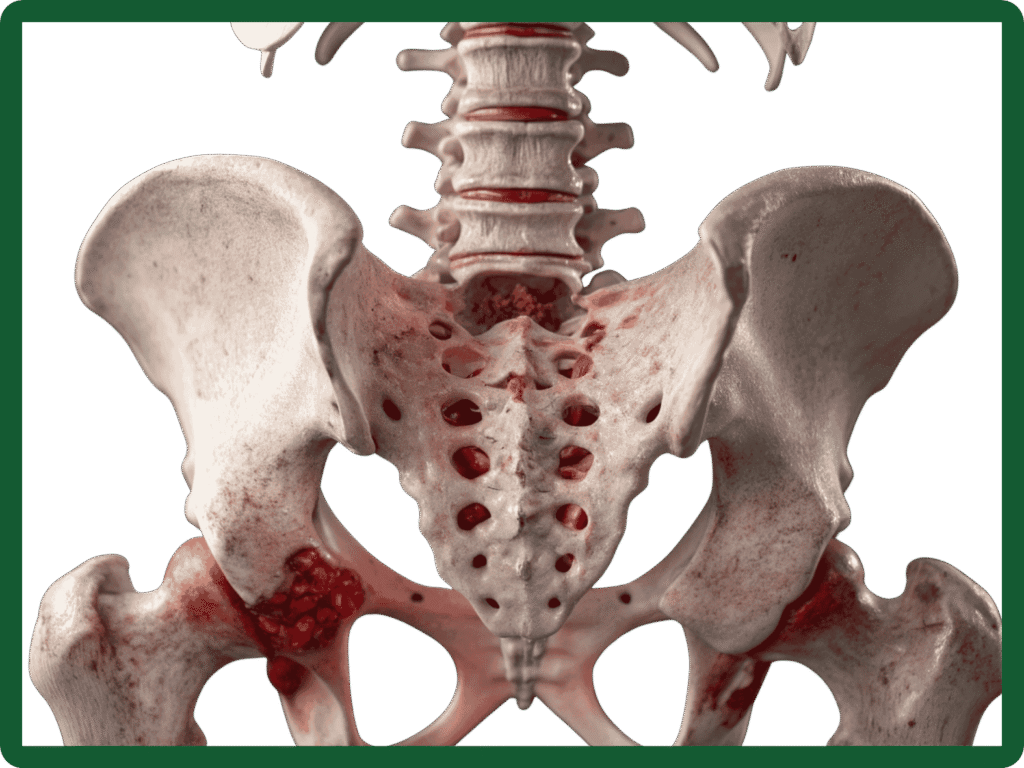

Hip arthritis is the wear-and-tear or inflammation of the hip joint that leads to pain, stiffness and reduced mobility. The hip is a ball-and-socket joint formed by the head of the femur (thigh bone) and the acetabulum (socket) of the pelvis. When the cartilage that cushions the joint wears away, bones rub together, causing pain and limiting everyday activities.

- Osteoarthritis (degenerative): The most common type where cartilage breaks down with age or overuse.

- Rheumatoid arthritis: An autoimmune inflammation affecting multiple joints.

- Post‑traumatic arthritis: Follows fractures or injuries to the hip.

- Avascular necrosis (osteonecrosis): Loss of blood supply to the femoral head leading to collapse and secondary arthritis.